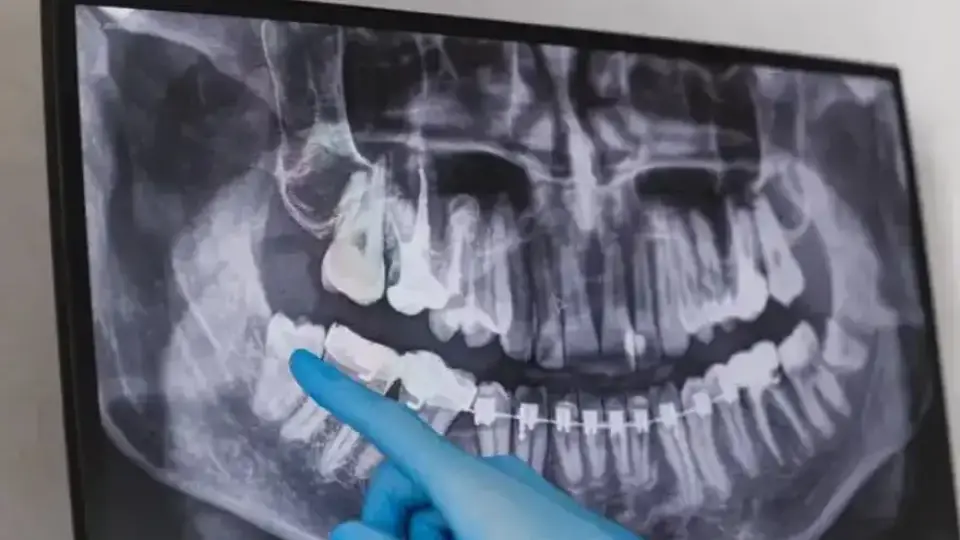

Зъболекарят се върнал със снимката от рентгена и цялото семейство замръзнало, опитвайки се да разбере какво точно вижда. На изображението ясно се виждало метално парче, заседнало в синусите на момичето.

Истината щяла да остане завинаги скрита, ако не бил стоматологичният преглед. Когато рентгеновата снимка се появила, тайната най-накрая излязла наяве.

Майката публикувала кадъра в платформата Reddit и снимката бързо станала вирусна.